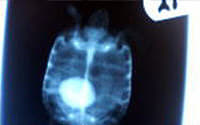

3診断

- レントゲン・超音波にて診断

- まれにレントゲンに映らないタイプがあるので注意

診断

上記写真の個体はどちらも完全に膀胱の中なので開腹手術適応

片方の個体は体重60グラムに満たない幼体